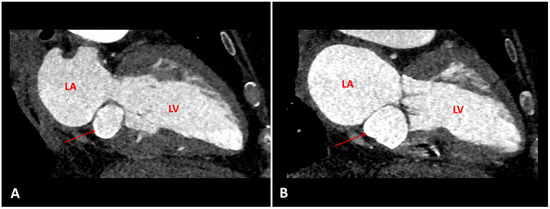

Myocardial infarction with nonobstructive coronary arteries (MINOCA): Myocardial infarction (MI) with non-obstructive coronary arteries (MINOCA) is defined as MI according to the fourth universal definition of MI [1] without coronary stenosis ≥50% on...